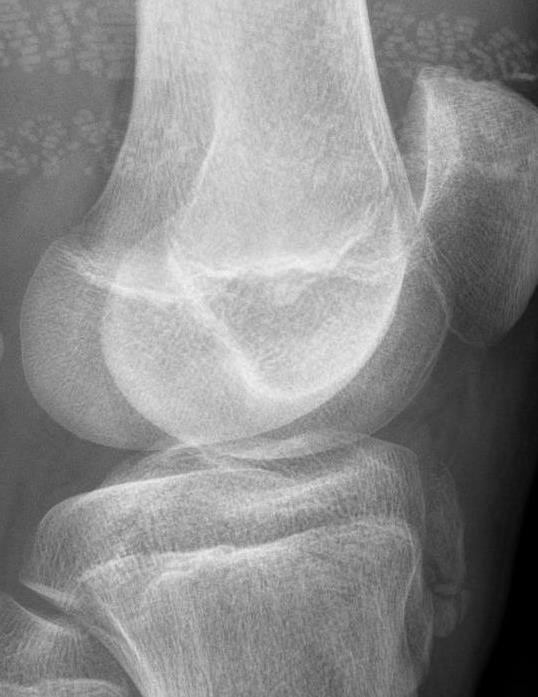

患者主要表现为膝痛,行走时明显,上下楼梯时或踢球等剧烈运动后加重,在一侧或双侧胫骨结节上端前方可触及局限性肿胀,伴有明显的压痛,晚期成年后,在胫骨结节处可触及肥大突起。X线片可显示胫骨结节骨骺呈舌状,骨骺骨质致密或边缘不规则,有时可见骨骺碎裂与骨干分离。